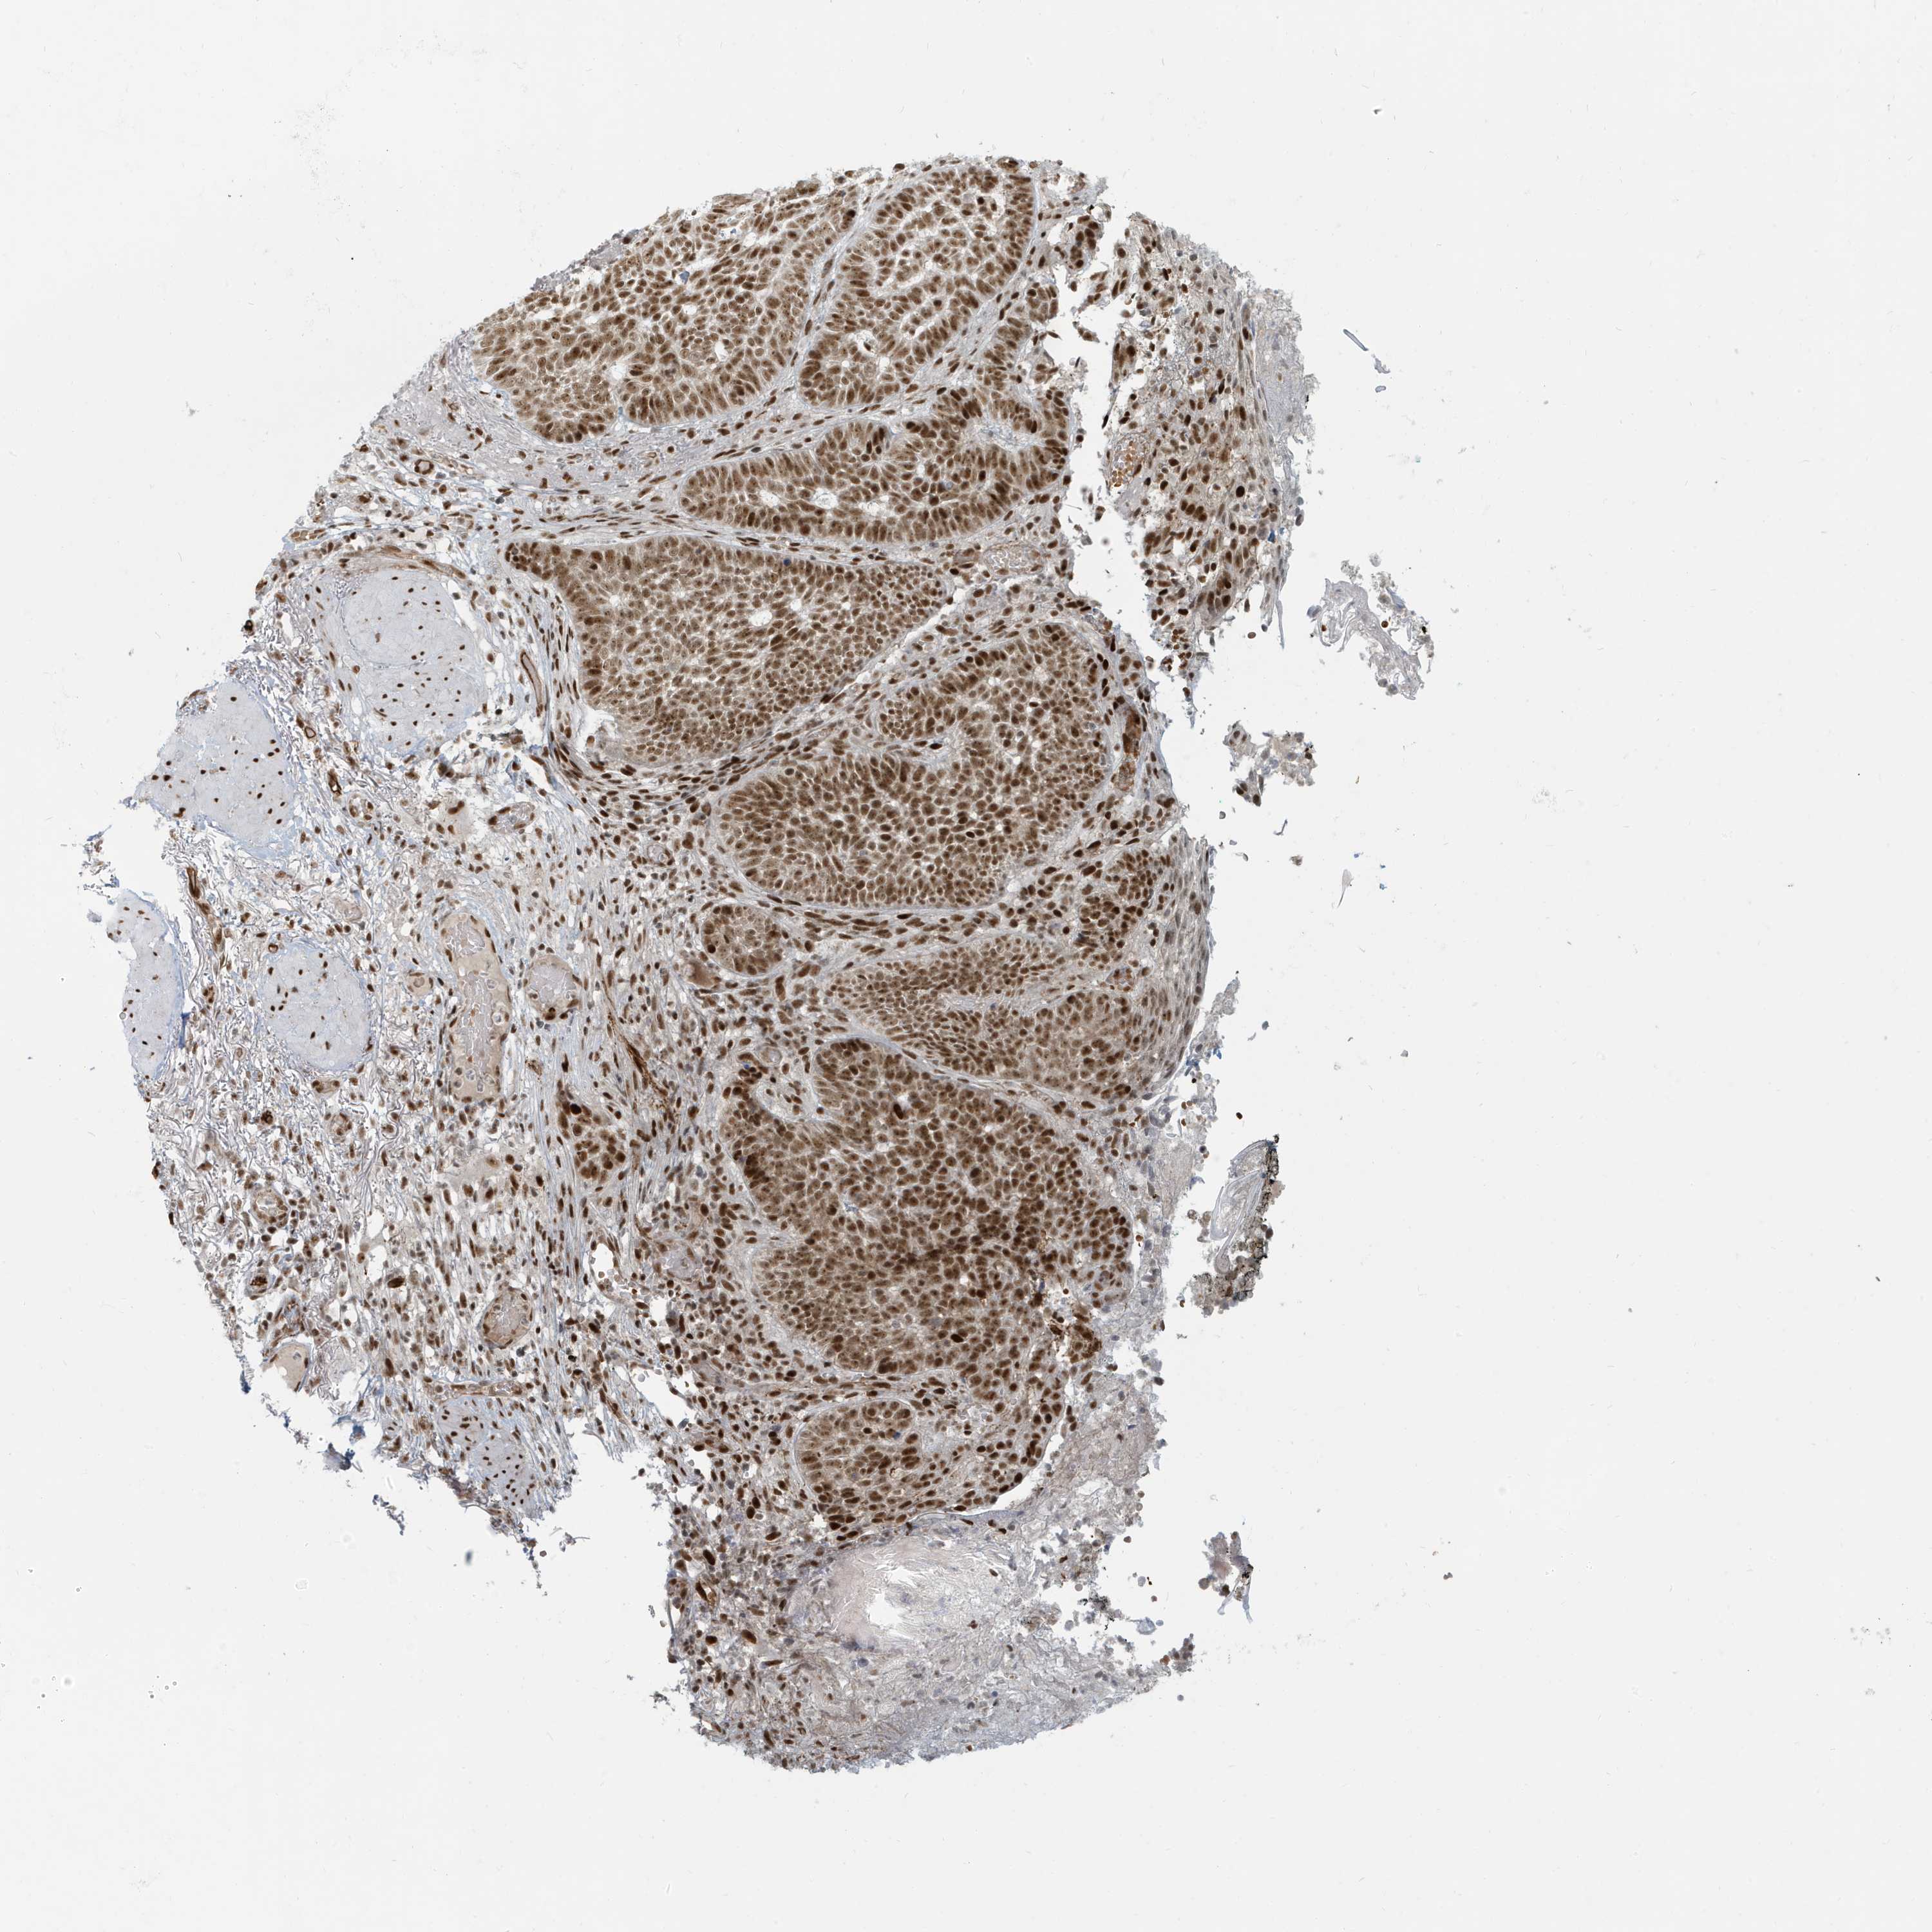

Basal cell and squamous cell cancer

SKIN CANCER - Protein expressioni

A mouse-over function shows sample information and annotation data. Click on an image to view it in a full screen mode. Samples can be filtered based on level of antibody staining by selecting one or several of the following categories: high, medium, low and not detected. The assay and annotation is described here.

Each image is clickable and will lead to virtual microscopy that enables deeper exploration of all samples and also displays staining intensity scores, fraction scores and subcellular localization as well as patient and tissue information for each sample.

Antibody HPA030762

Staining

High

Intensity

Strong

Quantity

>75%

Location

Nuclear

Basal cell carcinoma